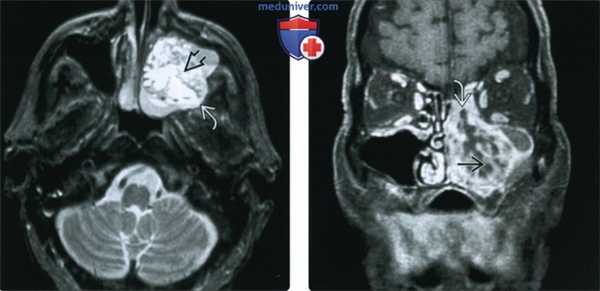

(Слева) На аксиальной КЛКТ в области правого клыка/премоляра определяется амелобластический рак. Обратите внимание на вздутие и перфорацию щечной кортикальной пластинки.

(Справа) Реформатированная КЛКТ альвелярного отростка у этого же пациента позволяет детально оценить вздутие и различимую глазом перфорацию щечной кортикальной пластинки, а также выраженную резорбцию корня 1-го премоляра.

4. МРТ при злокачественной амелобастоме и амелобастическом раке:

• Т1 ВИ:

о Солидные участки с сигналом промежуточной интенсивности

о Кистозные участки с однородным сигналом промежуточной интенсивности

• Т2 ВИ:

о Солидные участки с сигналом высокой интенсивности, накапливающие контраст на основе гадолиния

о Кистозные участки с сигналом высокой интенсивности контраст на основе гадолиния не накапливают

• Может обнаруживаться муральный узел или утолщение стенки